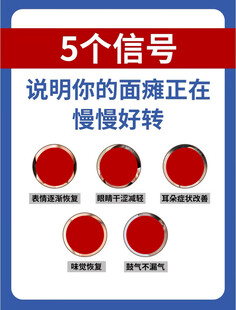

面瘫的5个信号 共享分:100

面瘫的5个信号 共享分:100 -